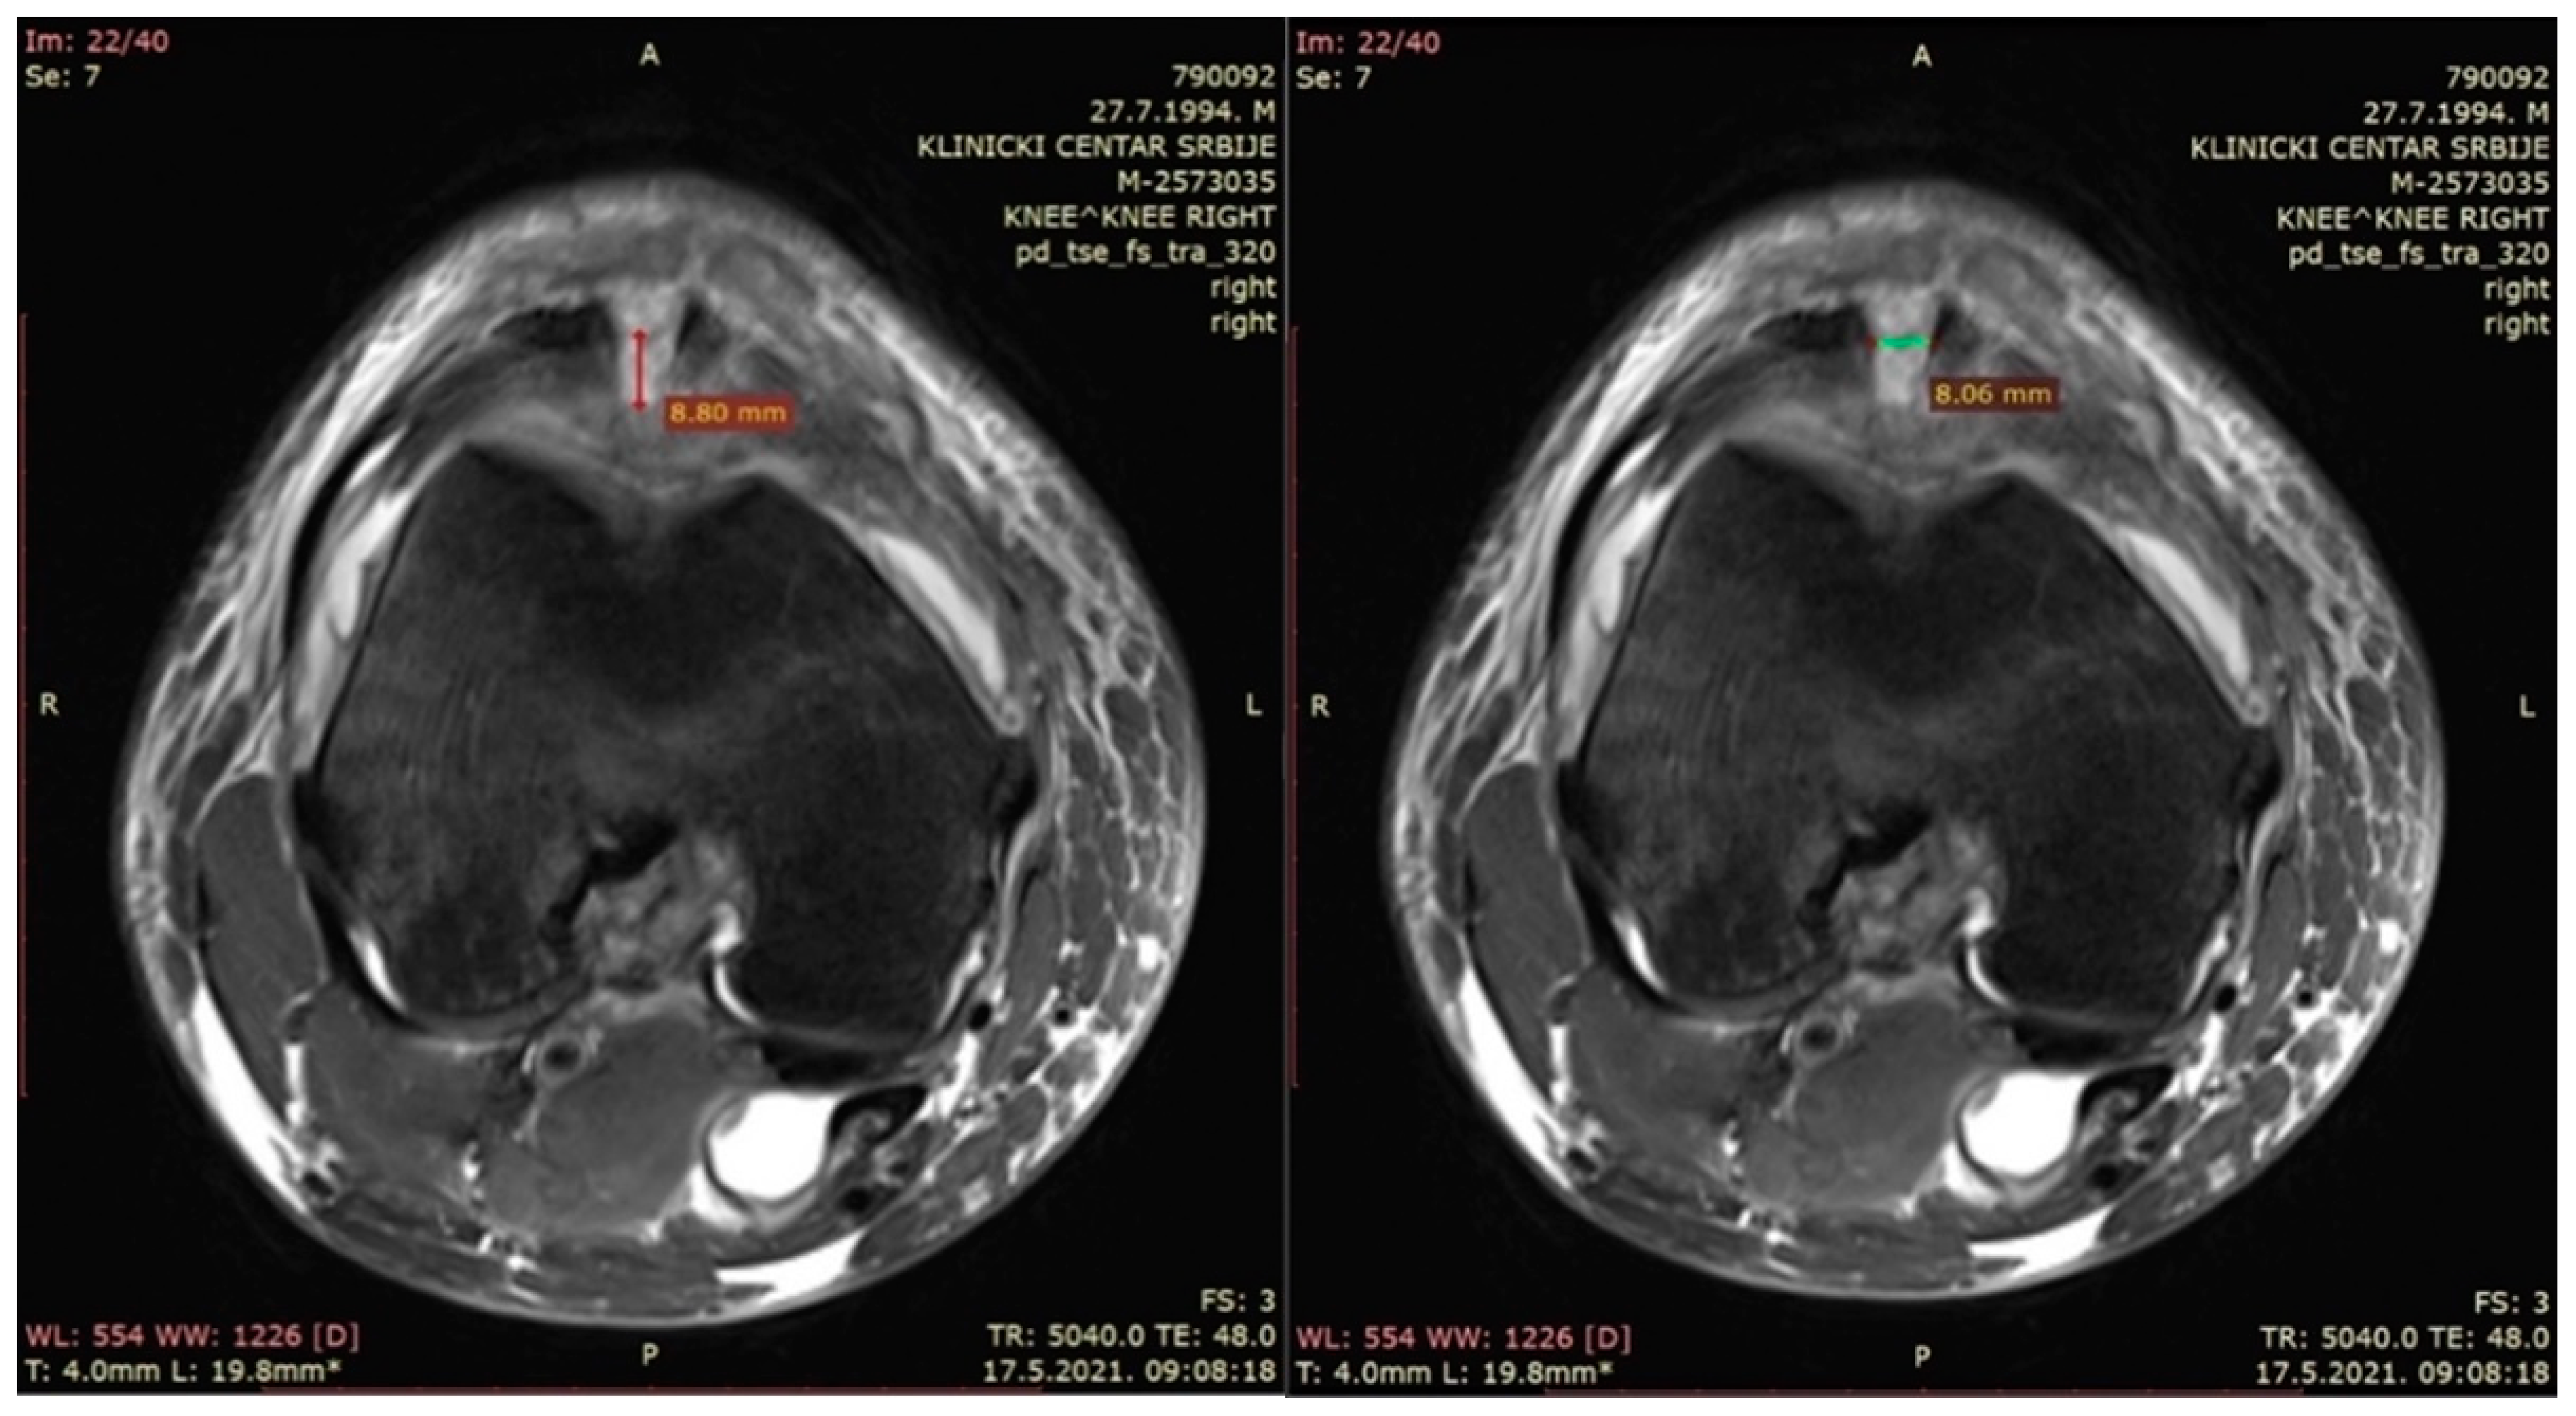

- The width of the patellar bone defect (mm)—a variable used to assess the width of the bone defect from the first section caudal to the top of the defect in a transverse plane in the pd_tse_fs_tra sequence (Figure 3—right).